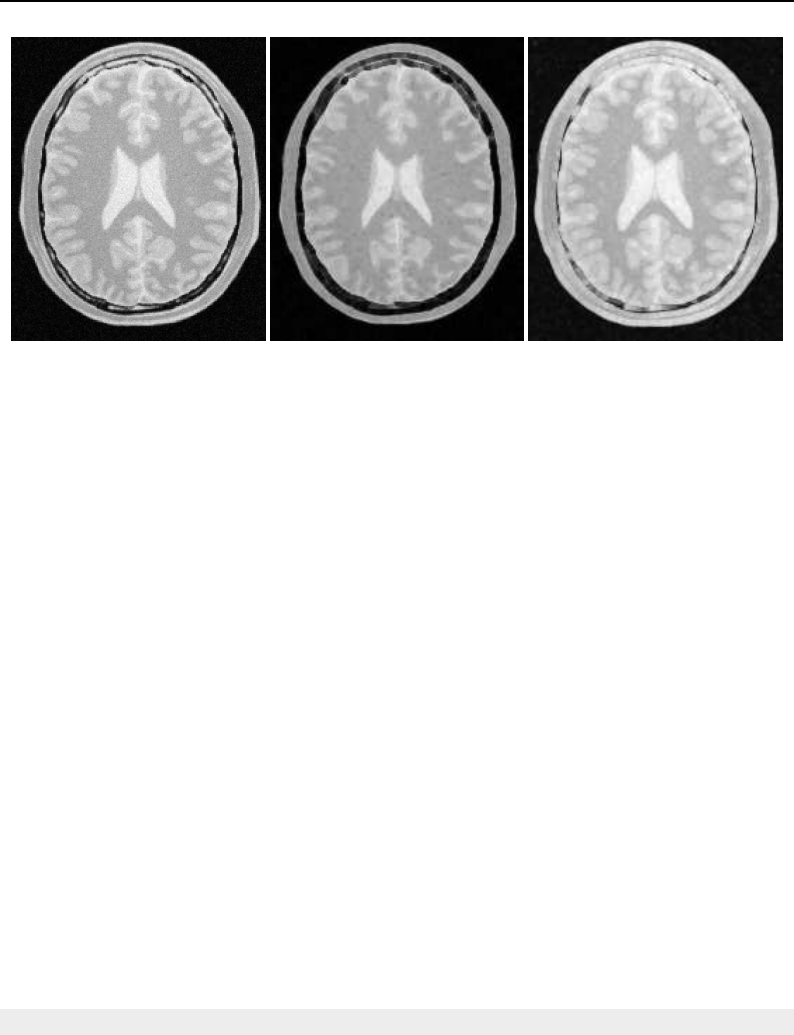

The Insight Toolkit (ITK) is an open-source, cross-platform system for medical image processing. It

provides medical imaging researchers with an extensive suite of leading-edge algorithms for

registering, segmenting, analyzing, and quantifying medical data. It is used in thousands of research

and commercial applications, from major labs to individual innovators.

The National Library of Medicine Insight Segmentation and Registration Toolkit, shortened as the

Insight Toolkit (ITK), is an open-source software toolkit for performing registration and segmenta-

tion. Segmentation is the process of identifying and classifying data found in a digitally sampled

representation. Typically the sampled representation is an image acquired from such medical instru-

mentation as CT or MRI scanners. Registration is the task of aligning or developing correspondences

between data. For example, in the medical environment, a CT scan may be aligned with a MRI scan

in order to combine the information contained in both.